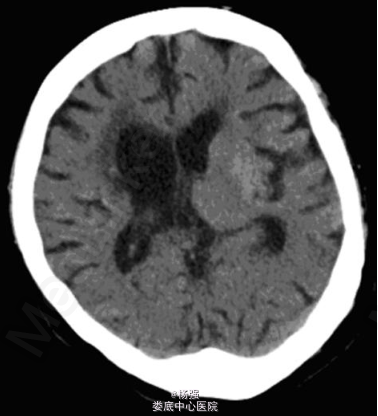

入院查体:血压120/70mmHg ,心肺腹(-),神清,言语不清,面部挤眉弄眼、撅嘴,右侧肢体不自主舞蹈样动作,肌力正常,肌张力稍高,右侧深浅感觉无明显异常,左侧肢体肌力 2-级,肌张力增高,左侧偏身痛觉障碍,左巴氏征(+),脑膜刺激征(-)。 入院后测静脉血糖 38畅28mmol/L;尿常规:糖(+++)酮体(-)。头颅 CT 提示左侧纹状体稍高密度灶,无占位效应,左侧小脑半球及右侧基底节区软化灶。

随访1年舞蹈样动作未再复发。出院后坚持预防脑卒中、控制血压血糖等治疗,血糖控制良好。讨论:糖尿病并发偏侧舞蹈症临床上较为少见 , 一般发生于血糖控制较差的糖尿病患者 , 常表现为急性或亚急性起病 , 单侧或双侧肢体不自主 、 不规则的舞蹈样动作及挤眉弄眼 、噘嘴 、伸舌 、面肌抽搐等无法控制的面部表情异常 。目前其发病机制尚不明确 , 可能与高血糖后的代谢紊乱 、 雌激素水平及种族差异等因素有关 。该病例需与脑梗死及脑出血相鉴别 , 纹状体梗死也可以引起舞蹈样症状 , 但患者左侧纹状体未见明显梗死灶 , 虽为高密度 , 但无占位效应 , 不支持出血诊断 , 结合患者老年女性 , 急起偏侧舞蹈症状 , 入院时检查符合非酮症性高血糖诊断 , 经积极控制血糖及硫必利 + 氯硝西泮治疗后症状好转 , 故诊断为糖尿病性非酮症性偏侧舞蹈病 。来源:《中国神经免疫学和神经病学杂志》Doi :10.3969/j.issn.1006-2963.2014.06.020